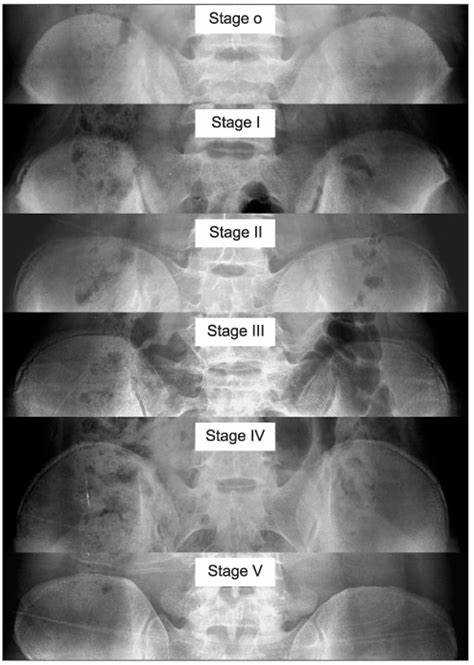

장골 골단의 골화는 Anterior Superior Iliac Spine 에서 시작하여 Posterior Superior Iliac Spine 까지 진행하게 됩니다. 골골화가 4단계 까지 진행된 후에 완전히 골화가 진행되어 5단계가 되게 됩니다.

각 단계마다 확인해보면 1단계는 25% 이하, 2단계는 25~50%, 3단계는 50~75%, 4단계는 75~100% 골화가 진행되는 것으로 분류하고, 5단계는 장골에 유합되는 것입니다.

Risser 4가 된 경우네는 척추의 성장이 종결되며

Risser 5에서는 더이상 뼈의 성장이 일어나지 않습니다. 고로 키가 더이상 크지 않을 것을 유추할 수 있습니다.